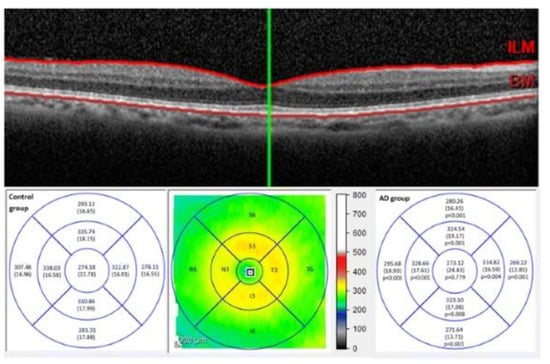

- Kim, B.J.; Irwin, D.J.; Song, D.D.; Daniel, E.R.; Leveque, J.S.; Raquib, J.L.; Pan, W.L.; Ying, G.-S.L.; Aleman, T.L.; Dunaief, J.L.; et al. Optical coherence tomography identifies outer retina thinning in frontotemporal degeneration. Neurology 2017, 89, 1604–1611. [Google Scholar] [CrossRef]

- Cunha, J.P.; Proença, R.; Dias-Santos, A.; Almeida, R.; Águas, H.; Alves, M.; Papoila, A.L.; Louro, C.; Castanheira-Dinis, A. OCT in Alzheimer’s disease: Thinning of the RNFL and superior hemiretina. Graefe’s Arch. Clin. Exp. Ophthalmol. 2017, 255, 1827–1835. [Google Scholar] [CrossRef]